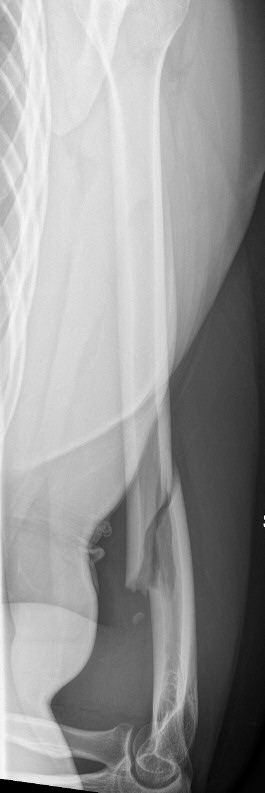

Exempel på humerusfraktur som behandlats icke-kirurgiskt, röntgenbilder efter 19, 40 resp. 71 dagar